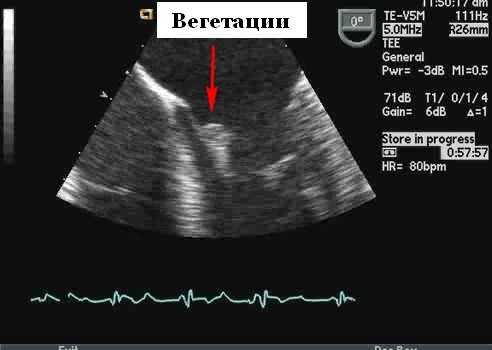

- Вегетации (подвижные образования на клапане, движутся в сердечном цикле, но их часто трудно увидеть)

- M-режим может отображать вегетации в виде нескольких толстых эхо-линий, наложенных на M-режим протеза, но и M-режим, и 2D-эхокардиография могут быть затруднены из-за реверберации и маскировки. Небольшие вегетации (

- Допплерография и цветовой поток могут показать гемодинамические последствия эндокардита - чресклапанную регургитацию (вегетации, влияющие на закрытие створки), парапротезную регургитацию (образование абсцесса на линиях швов) или усиление потока вперед из-за препятствия кровотоку вегетациями. Как уже упоминалось, в этих ситуациях очень полезна чреспищеводная эхокардиография.

Вегетации имеют ряд типичных эхокардиографических характеристик, и диагноз обычно может быть установлен с относительно высокой степенью уверенности с помощью эхокардиографии в сочетании с клинической симптоматикой. Они кажутся менее отражающими (серыми) по сравнению с нормальной тканью клапана и расположены перед клапаном на линии струи регургитации (предсердная поверхность митрального клапана и поверхность желудочков створок аорты). Обычно они выглядят дольчатыми с неровными, плохо очерченными границами и имеют хаотическое движение, в отличие от других клапанных образований (фиброэластомы и т. д.), которые имеют тенденцию к более высокому отражению, с четко определенными границами и менее хаотичным движением. Тонкие протяженные клапанные прикрепления с узким основанием, скорее всего, будут неинфекционными фибринозными нитями, чем вегетациями. Признаки, которые помогают отличить вегетации от других образований, включают наличие разрушения створки, регургитации клапана и образования абсцесса или свища. Сообщается, что чувствительность трансторакальной эхокардиографии для выявления признаков эндокардита составляет от 44 до 60%, по сравнению с чувствительностью 88 и 100% для ЧПЭхоКГ. Мелкие вегетации ( 90%), хотя при более высоком разрешении чреспищеводной эхокардиографии повышенная чувствительность может происходить за счет немного сниженной специфичности (возможность маркировать небольшие доброкачественные фибринозные тяжи на нативных и протезных клапанах или незначительно подвижные шовный материал на протезах клапанов в виде мелких нитей).